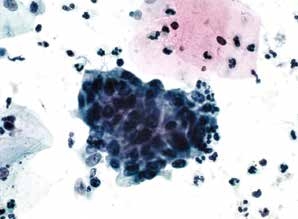

图7-17 子宫颈管/移行区成分的几点说明(高倍、液基、巴氏染色)

查见异常细胞,可以不报告移行区的改变。图示为鳞状细胞癌。